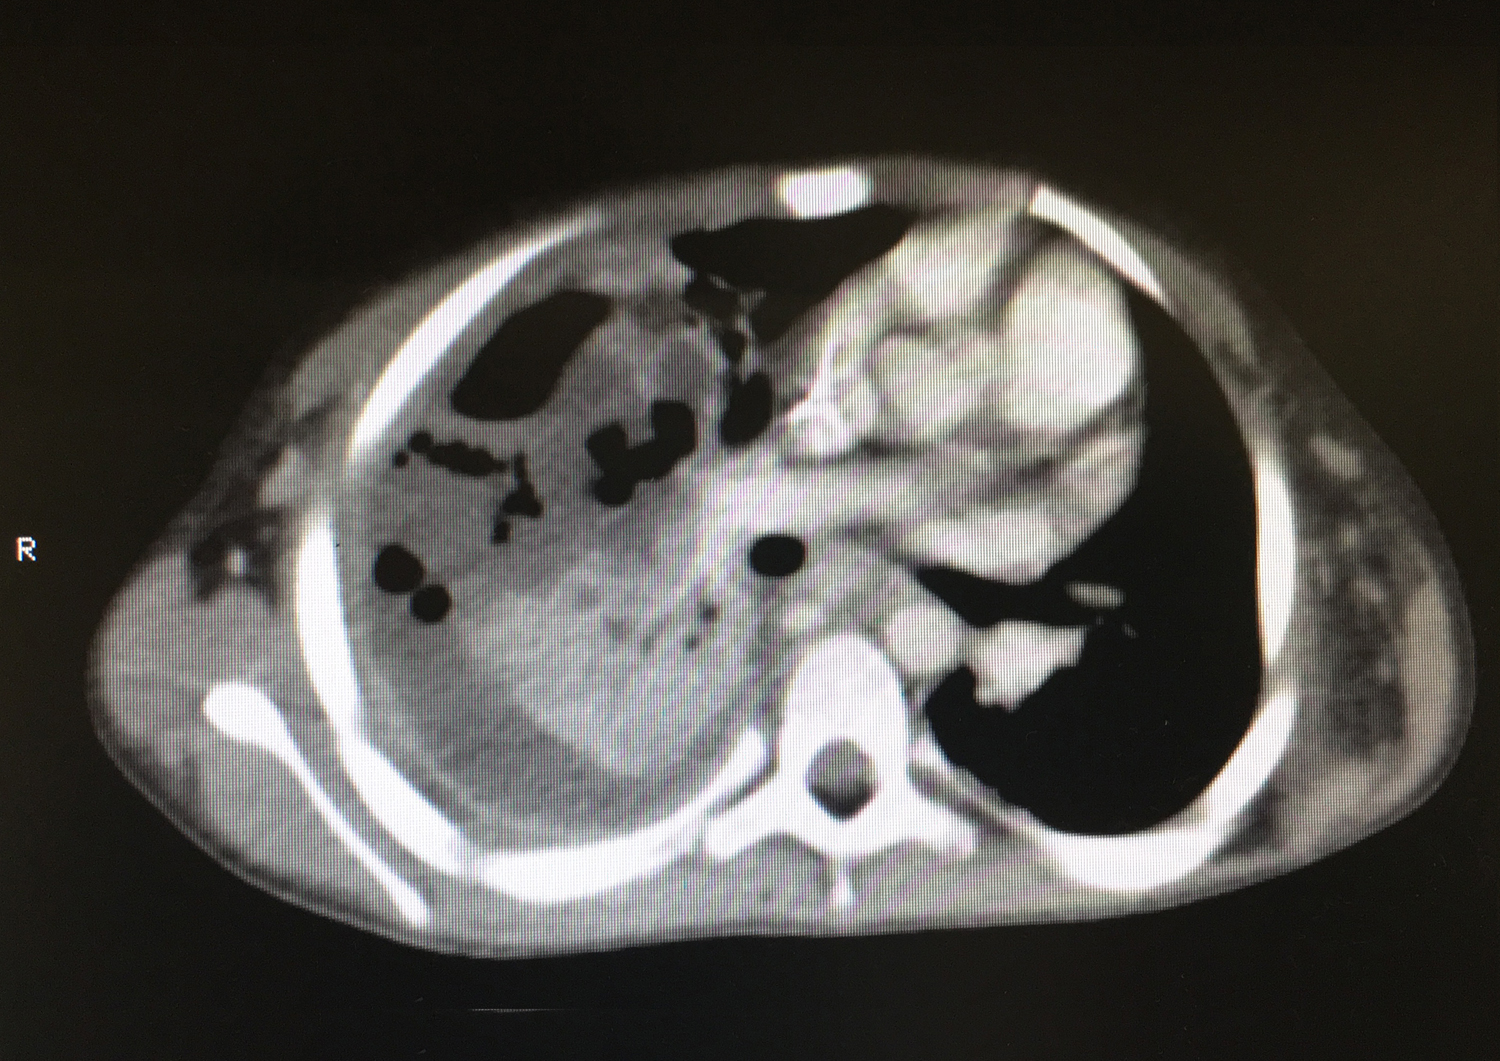

A los cinco días de ingreso se realiza una TC de tórax por el aumento de dificultad respiratoria persistente sin débito por drenaje pleural, que muestra una neumonía necrotizante en el lóbulo superior derecho, asociada a un pequeño hidroneumotórax. Se retira en las siguientes 48 horas el drenaje pleural ante débito nulo por el mismo y no observarse mayor afectación en la tomografía computarizada (TC).